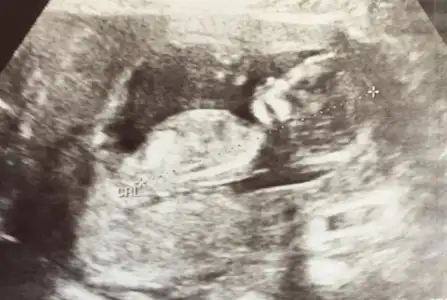

Maşallah kıza benzettim benMerhaba herkese. Dayanadim ozeldeki doktoruma geldim:) her sey yolundaymis. Devletteki olcumler hatali oldugu gibi cogu seye de bakmamis. Artik ben de bir tahmin rica ederim :)